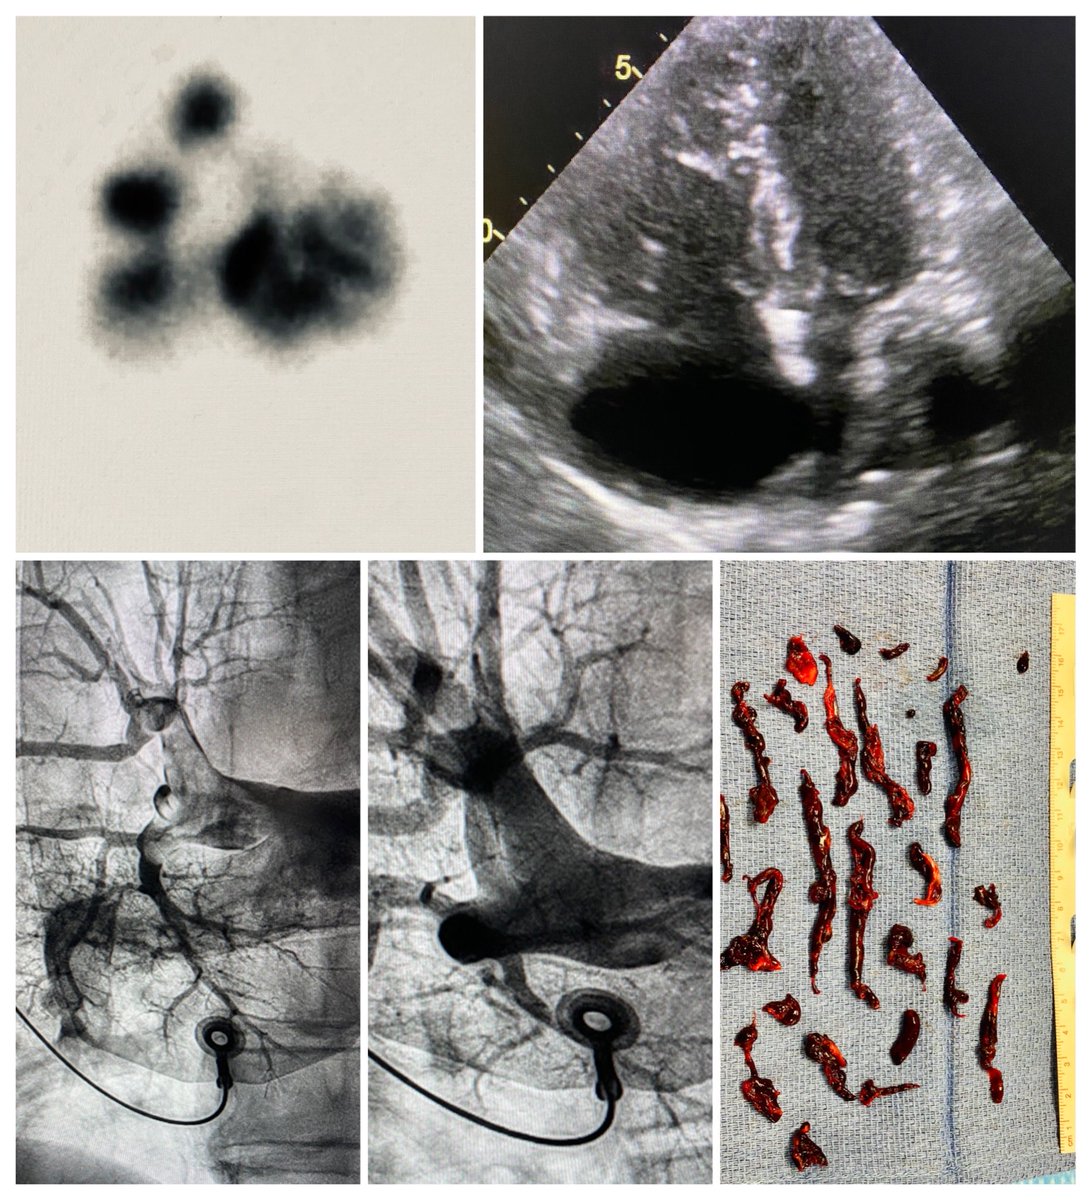

When it quacks like a duck: (no CTA due to CKD/ARF): hypoxemia, d-dimer, V/Q, RVD on echo. 12F computer assisted thrombectomy. 20 cc contrast.